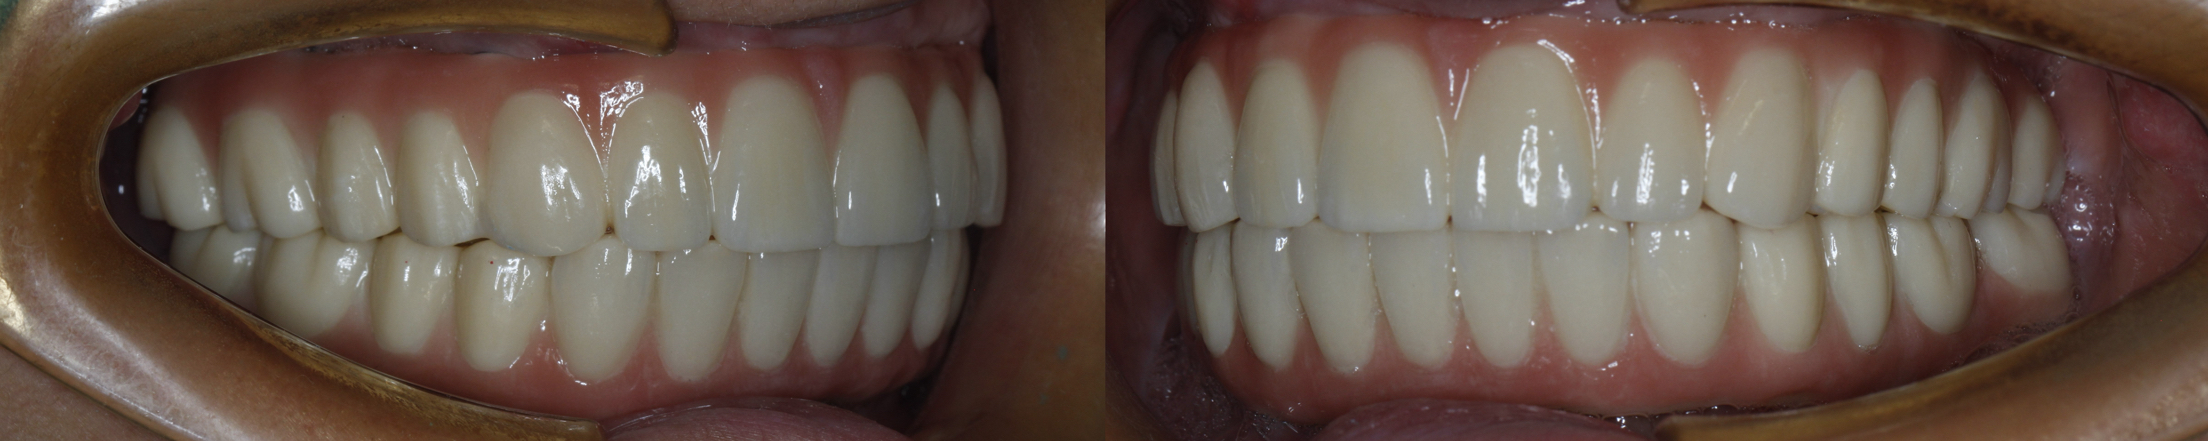

该患者就是因牙周病导致牙齿松动脱落,我们通过在全口牙槽骨上植入16颗种植体,然后在种植体上安装连桥牙冠,从而恢复半口牙齿的咀嚼功能和美观。相对于传统的种植修复方式缺一颗种一颗。4-8颗种植体的种植手术创伤相对较小,大大的减少了患者的疼痛感。

种植牙是当前缺牙修复的理想选择,但成功与否依赖医生技术、患者自身条件和术后维护。尽早修复缺牙,才能避免邻牙倾斜、咬合紊乱等问题,重获健康笑容。